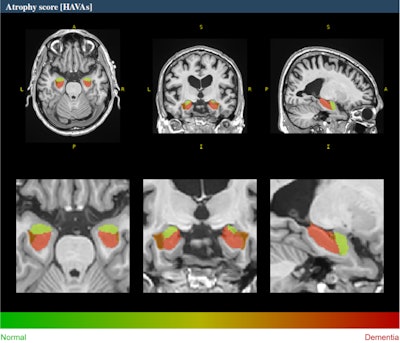

Example of HAVA score using the volBrain platform for a 70-year-old male with late mild cognitive impairment. All figures courtesy of Dr. Alexandru Fulga et al and presented at ECR 2024.

A novel deep-learning-based tool for Alzheimer's detection and mild cognitive impairment prognostic has been developed, relying on estimated lifespan trajectories of brain structures, the authors explained. Hippocampal-amygdalo-ventricular Alzheimer scores (HAVAs) are based on lifespan models of normal population and Alzheimer's patients, which after validation showed a great capability of detecting patients with Alzheimer's compared with control subjects and specific discrimination between progressive and stable mild cognitive impairment.

The pipeline is freely available and integrated into the volBrain online platform (see: volBrain: An Online MRI Brain Volumetry System, Front Neuroinform, 27 July 2016). It generates volumes of the hippocampus, amygdala, and inferior lateral ventricle, graphics showing where the patient's values stand between the estimated lifespan trajectories of healthy and Alzheimer's patients and it also calculates a probability score based on the three regions analyzed. The method has shown considerable accuracy both in the diagnostic task and the prognostic task.